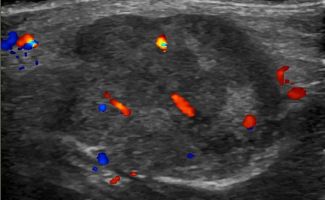

Πολλές αλλοιώσεις και παθήσεις μπορούν να απεικονιστούν υπερηχογραφικά και να μελετηθούν αξιόπιστα με τη βοήθεια του Έγχρωμου Doppler και της Ελαστογραφίας .

- Αιμαγγειώματα, αγγειοδυσπλασίες (αγγειακού τύπου βλάβες)